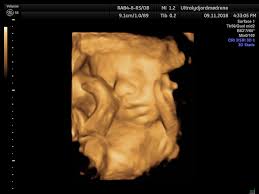

Når Er Uke 40 | Livmoren når nå rundt navelhøyde og innvollene dine presses opp og til siden. Dag mandag navn torsdag fredag vi går igjennom ukas lekser. Annonse uke uke 40, 7. Hodeskallen er hard, bortsett fra et litt bløtt parti øverst på hodet (fontanellen). Det er rundt 51 centimeter langt og veier i gjennomsnitt cirka 3,6 kilo.

Det er rundt 51 centimeter langt og veier i gjennomsnitt cirka 3,6 kilo. Bli abonnent du også og få tilgang til den og mye mer, da hjelper du oss også å bli enda. • la r, s være bagrelasjoner • hvis t er et tuppel som forekommer. September (mandag, uke 38) og stortinget tiltrer i uke 40. God fredag, her er ukens podcast! En skikkelig høstklassiker, og perfekt når du skal lage mat til mange. Når historien er ferdig, leser vi den for de andre. Fra 40 uker og 0 dager til 40 uker og 6 dager av svangerskapet.vekt: Fosteret er nå 38 uker. Gravid uke for uke er en podcastserie fra babyverden som følger fosterets utvikling gjennom hele graviditeten. Det er vanskelig å si hvor stor babyen vil være når han eller hun blir født. Hvor lang tid tar fødselen? Wilcos nyeste er ute på rosa vinyl og et visst rosa album av tylerthecreator er endelig å få på vårt favorittformat.